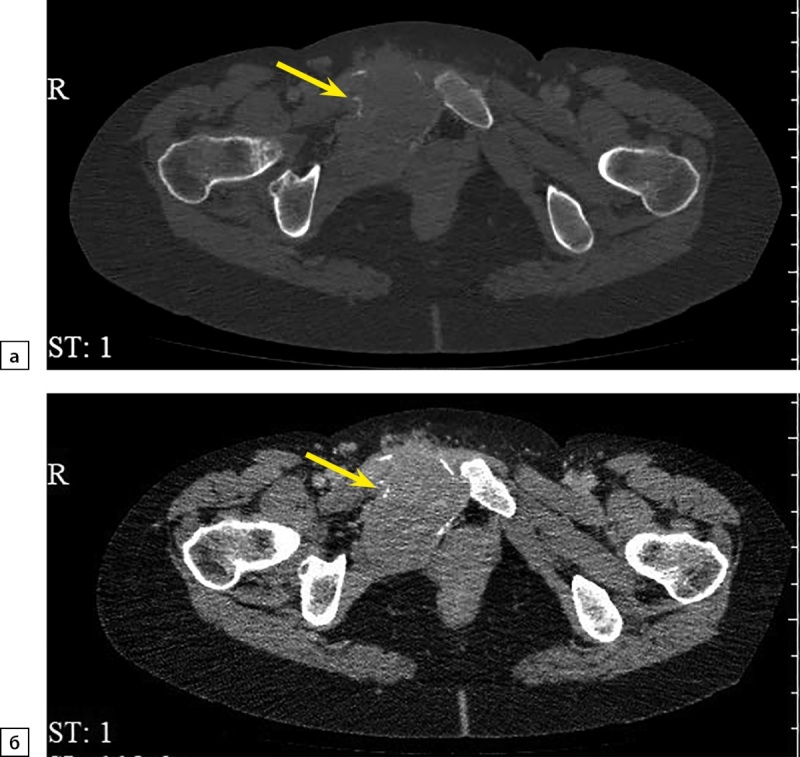

嗜铬细胞瘤(PHEO)目前被认为是恶性的,由于转移的潜力。最常见的家族性PHEO之一是多发性内分泌瘤变综合征(MEN) 2型。PHEO在MEN2综合征中的外显率高达50%。它可能是单侧或双侧,但转移发生极为罕见。在大多数MEN2综合征病例中,远处转移的来源是甲状腺髓样癌(MTC),这一事实使PHEO转移病例的鉴别诊断复杂化。本文报道了MEN2患者中PHEO转移至淋巴结、肺、肝、骨、脑的孤立病例。在现有文献中,我们发现了31例MEN2综合征转移性PHEO的描述。这些案例的可用数据以表格的形式呈现在本文中。我们报告了一名40岁女性MEN2A综合征(RET原癌基因p.Cys634Tyr突变),有两次手术治疗MTC的病史,每日伴有动脉高血压危像,伴有植物性症状,伴有巨大的双侧PHEO(右侧达200米,左侧达150毫米),同时伴有大转移(高达50毫米)进入耻骨并破坏。患者接受了几次手术:双侧肾上腺切除术,然后是双侧颈部翻修,切除右上、右下甲状旁腺,残余甲状腺组织,然后切除右耻骨肿瘤。

Pheochromocytoma (PHEO) currently is considered to be malignant due to metastatic potential. One of the most common familial forms of PHEO is multiple endocrine neoplasia syndrome (MEN) type 2. The penetrance of PHEO in MEN2 syndrome is up to 50% of cases. It may be one- or two-sided, but metastases occur extremely rare. The fact that in majority of cases of MEN2 syndrome the source of distant metastases is medullary thyroid carcinoma (MTC) complicates differential diagnosis in case of PHEO metastasis.Isolated cases of PHEO with metastases to the lymph nodes, lungs, liver, bones, brain in MEN2 patients were described. In the available literature, we have found a description of 31 cases of metastatic PHEO in MEN2 syndrome. The available data of those cases is presented as a table in the article.We present a description of a 40-year-old woman with MEN2A syndrome (mutation of the RET proto-oncogene p.Cys634Tyr), with a history of twice-performed surgical treatment of MTC, with daily crises of arterial hypertension accompanied by vegetative symptoms, with a giant bilateral PHEO (up to 200 m on the right and up to 150 mm on the left) with synchronous large metastasis (up to 50 mm) into the pubic bone with the destruction. The patient underwent several surgeries: bilateral adrenalectomy, then a bilateral revision of the neck, removal of the right upper and right lower parathyroid glands, residual thyroid tissue, then resection of the right pubic bone with a tumor.